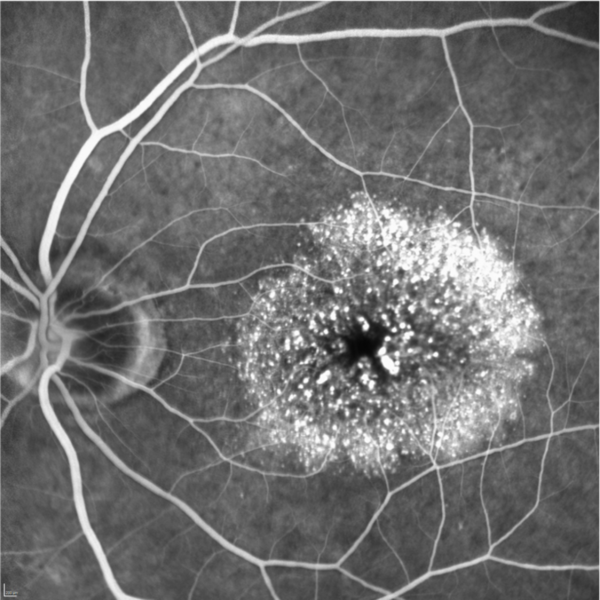

L’angiographie est un examen d'imagerie rétinienne qui permet d’étudier les vaisseaux sanguins non visibles sur simples clichés du fond de l'oeil. Elle a pour but de détecter des troubles de la vascularisation mais aussi d'apprécier la qualité des tissus rétiniens. Elle reste l'examen de référence pour le diagnostic de la plupart des pathologies rétiniennes et maculaires.

Il existe deux types d'angiographie, l'angiographie à la fluorescéine, et l'angiographie au vert d'indocyanine (ICG) utilisant des colorants différents et permettant de visualiser différemment la rétine et la choroïde.